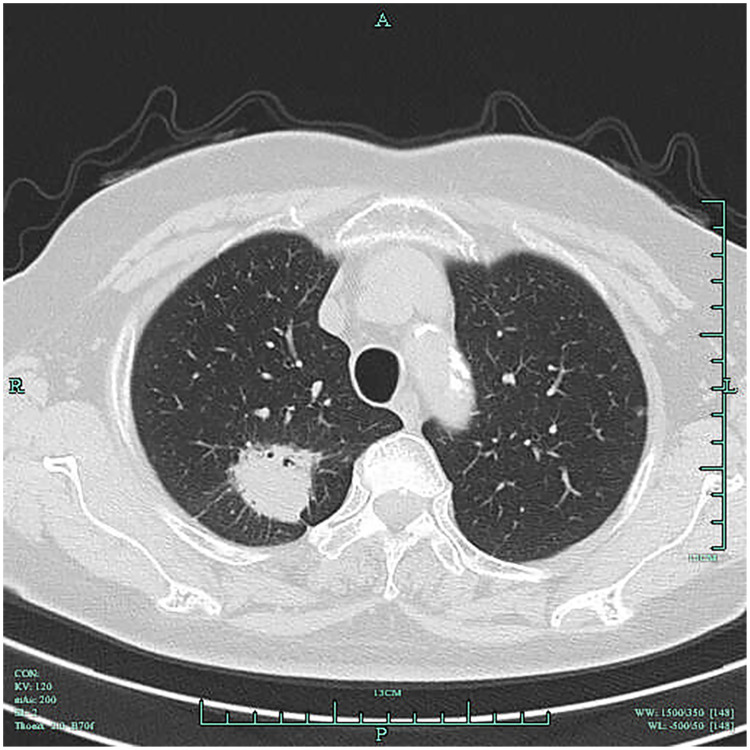

Purpose: Early detection of lung cancer is critical to improving prognosis, yet current screening methods such as low-dose spiral CT and serum CEA each have diagnostic limitations. This study aims to analyze the clinical value of low-dose spiral CT combined with serum CEA in the differential diagnosis of early lung cancer.

Materials and methods: In this retrospective study, 62 patients diagnosed with early lung cancer in our hospital from April 2022 to October 2023 were selected as the case group, and 50 patients diagnosed with benign pulmonary lesions during the same period were selected as the control group. Data from low-dose spiral CT and serum CEA levels were compared. The efficacy of low-dose spiral CT alone, serum CEA alone, and the combination of both in discriminating early lung cancer was assessed using ROC curves.

Results: Low-dose spiral CT showed a sensitivity of 77.42%, a specificity of 94.00%, and an AUC of 0.8571 (95% CI: 0.7832-0.9310) in detecting early lung cancer. Serum CEA levels were significantly higher in the case group compared to the control group (P<0.05). Serum CEA yielded an AUC of 0.8661 (95% CI: 0.7964-0.9359) in distinguishing early lung cancer (P<0.0001). Low-dose spiral CT combined with serum CEA detection achieved an AUC of 0.9137 (95% CI: 0.8624-0.9650), significantly increasing the early lung cancer detection rate from 82.26% to 95.16% (P<0.05).

Conclusion: Patients with early lung cancer show distinct alterations in low-dose spiral CT signs, and their serum CEA levels demonstrate a notable increase compared with those with benign pulmonary lesions. The combination of low-dose spiral CT with serum CEA can be considered in the discrimination of early lung cancer, which can markedly enhance the positive detection rate while maintaining a minimal rise in false-positive rates.